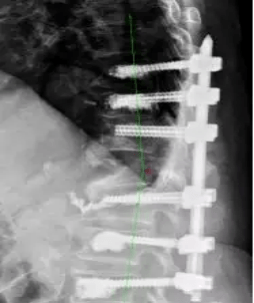

腰椎间盘突出症折磨人,微创脊柱内镜来帮忙多年的腰椎间盘突出症突然加重,腰腿痛导致行走和睡眠受到严重影响。经同学介绍找到脊柱外科杨小卫医生,术前检查诊断为腰椎间盘突出症,椎管横截面压迫近9成,耽误病情很容易造成马尾综合征等严重并发症。杨小卫医生介绍到:微创内镜下手术后第二天可以下床活动,术后三天顺利...

中山一院贵州医院开展全省首例LUSE技术下腰椎间盘切除术技术下腰椎间盘切除术。这一手术的顺利完成,不仅标志着贵州在脊柱微创治疗领域取得了重大突破,更为众多腰椎间盘突出患者带来了康复的... 决定为患者实施LUSE技术下腰椎间盘切除术。这种手术方式具有创伤小、恢复快、并发症少等诸多优势,能够精准地去除突出的椎间盘组织,缓...

医生研究发现:一旦做过腰椎手术,这5件事就别做了?清晨的社区医院走廊里,58岁的张阿姨扶着腰慢慢挪步。三年前她因腰椎间盘突出做了微创手术,术后恢复良好,但最近弯腰系鞋带时突然闪过剧痛。"明明当时医生说手术很成功,怎么现在又不舒服了?"她攥着检查报告的手微微发抖,报告上"椎间隙感染"四个字格外刺眼。临床数据显示,我国...

有“镜”无险 毫米破局 九旬老人一小时告别腰突顽疾专家科普:老年腰突特点与微创优势 老年腰椎间盘突出症患者常合并椎管狭窄及钙化,保守治疗效果有限,致残风险较高。脊柱内镜微创手术具有以下优势: 超微创伤、安全性高:局麻即可进行,出血少,对脊椎稳定性影响小。 精准高效、恢复快:针对病变节段进行精准减压,术后2-3天即...